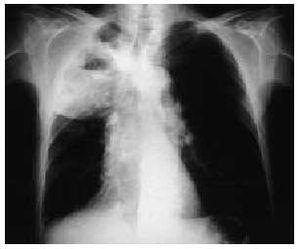

En la radiografía de tórax se observaba una masa cavitada que ocupaba la totalidad del lóbulo superior derecho (figs. 1 y 2).

Fig. 1.